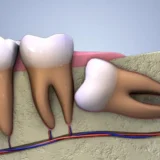

Mất răng ảnh hưởng sinh hoạt, ăn uống và gây thẩm mỹ cho người bệnh. Đặc biệt, đối với khu vực răng hàm, việc mất răng ảnh